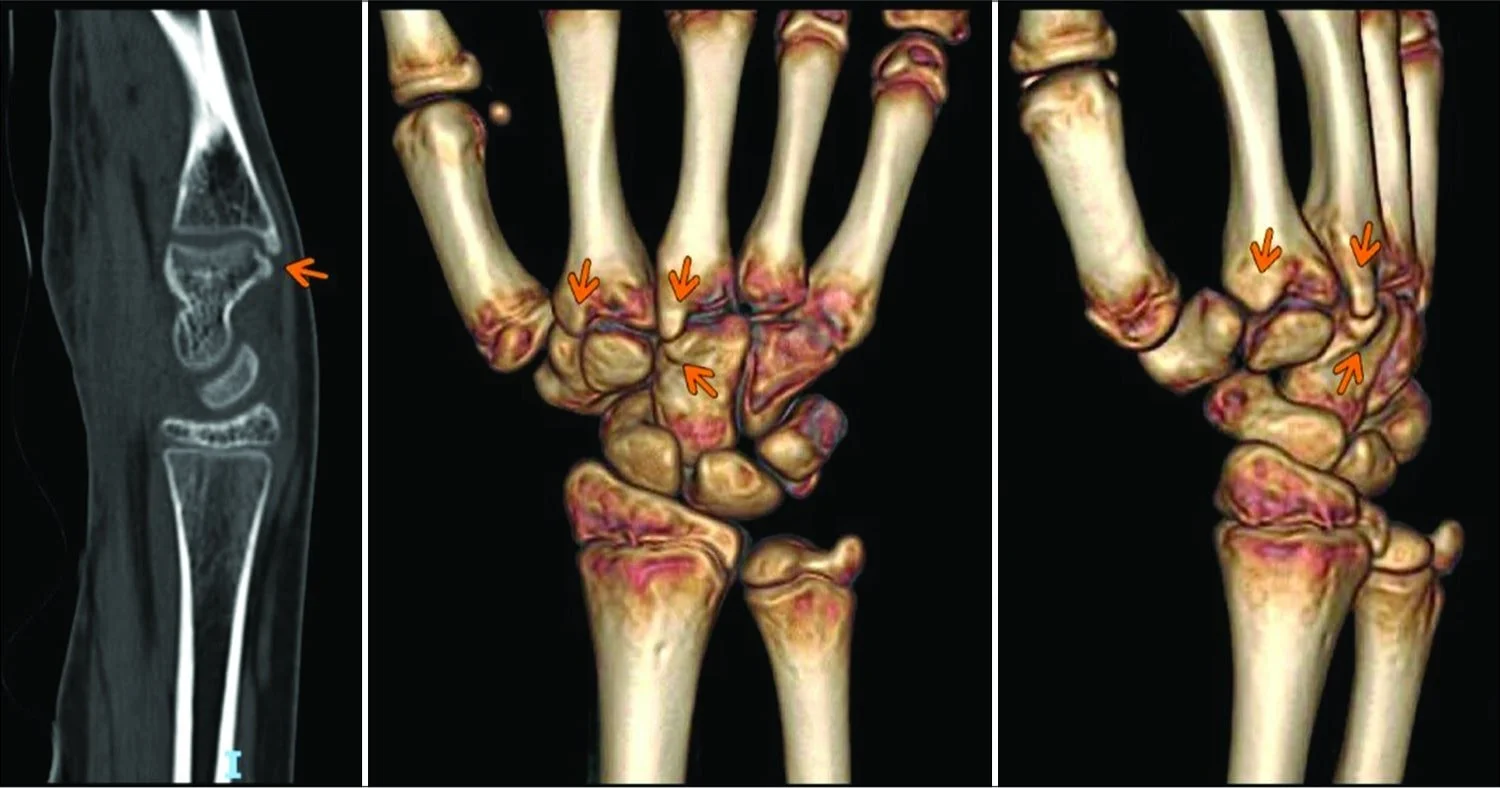

CT and 3D scans of wrist bones with arrows highlighting abnormal bone growth — illustrating possible causes of a hard bump that feels like a bone.

The carpal boss, is often discovered as a hard lump on the back of the hand near the wrist (1). It’s an overgrowth of bone or cartilage, asserting itself where the tendons of the hand and wrist flex and move. While its name suggests authority, a carpal boss is usually benign. Its presence may be completely asymptomatic, but for some, it may lead to stiffness or discomfort with certain wrist movements. The causes are not entirely clear, though repetitive strain or a history of trauma could be contributing factors. Managing a carpal boss ranges from non-invasive approaches like rest and immobilization to more definitive treatments like surgical removal for those who experience persistent discomfort or limitation in movement.